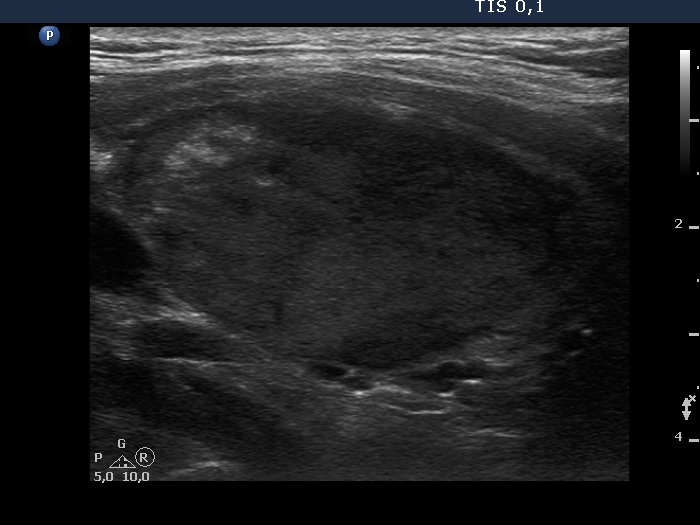

Clinical presentation: A 41-year-old man was referred for aspiration cytology. First, he was examined for nodular goiter 9 years ago when FNA resulted in benign colloid goiter from a nodule with a 21-mm maximal diameter. Recently, cytology was repeated because the nodule has been grown to 42 mm. This time FNA was non-diagnostic.

Ultrasonography. The thyroid was echonormal. There was a hypoechoic nodule in the right lobe. The dimensions of the nodule were 39x21x42 mm, width, depth and length, respectively. The lesion had a partial halo and both perinodular and intranodular vascularity.

Considering the ultrasound presentation, we gave a combined sono-cytological diagnosis of suspicion of follicular tumor.

1. On the ultrasound presentation, the likelihood of follicular tumor is around 90%.

3. In a large solitary nodule presenting either halo or perinodular vascularity, the likelihood of a follicular tumor is greater than 90%.